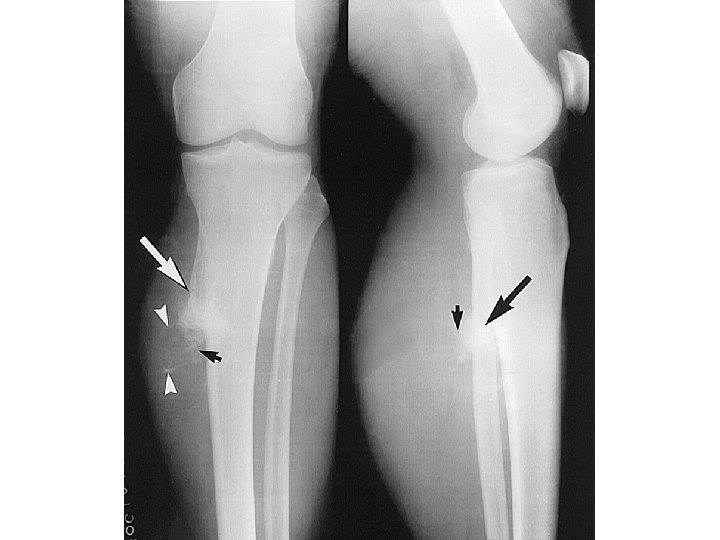

DESCRIBE FRACTURE FRAGMENTS

ANSWER • This is a closed midshaft tibial fracture…. But how do we describe the fragments? • This is an example of partial apposition; note part of the fracture fragments are touching each other • Alternatively you can describe this as displaced 1/3 the thickness of the bone • Remember aposition and displacement are interchangeable—we tend to describe displacement • Final answer: Closed midshaft tibial fracture with moderate (33%) displacement